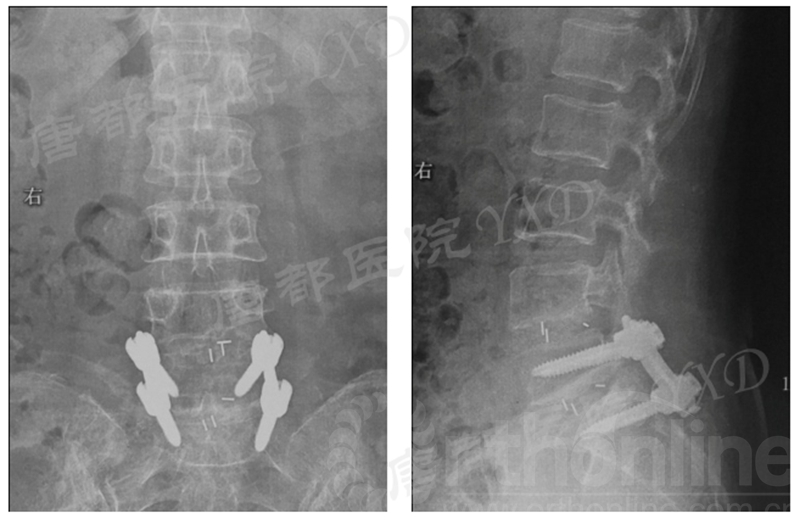

既往8年前因“腰4、5椎弓峡部裂并腰4椎体滑脱症”于外院行腰4~骶1椎板减压椎间植骨融合内固定术,后因椎弓根螺钉断裂于5年前行内固定取出术。

影像学检查:

诊断:腰椎椎间融合术后融合器后移

手术方案:显微镜辅助MI-TLIF腰椎翻修术